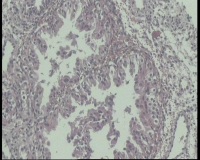

| 图片: | |

- 急!请老师看看34岁子宫内膜

| 性别 | 女 | 年龄 | 34岁 | 临床诊断 | 子宫内膜息肉? |

| 一般病史 | 末次月经:11月20日,近两个月无诱因性生活有阴道少许血性分泌物 | ||||

| 标本名称 | 宫内容物 | ||||

| 大体所见 | 膜样碎组织3.0厘米 | ||||